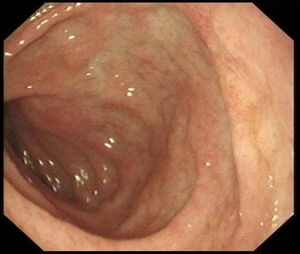

胃镜检查:反流性食管炎A级

萎缩性胃炎

十二指肠黏膜结节不平原因待查

十二指肠降段巨大憩室

胃镜影象